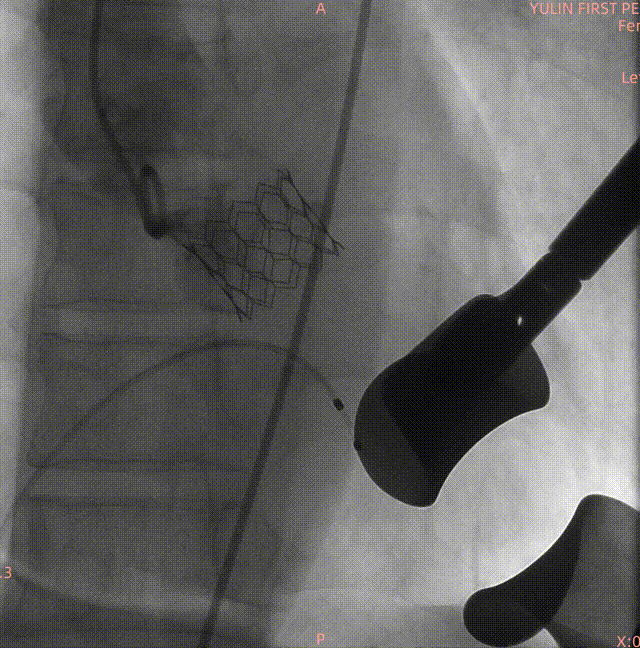

23#Renatus瓣膜释放中再次造影定位

释放后造影示瓣膜位置理想,形态良好

通过术前精准评估,患者在全麻下行TAVR手术,DSA和食道超声双重引导,通过右侧股动脉建立工作路径,沿加硬导丝送入19mm*40mm球囊预扩张主动脉瓣,预扩时双侧冠脉显影良好。退出预扩张球囊后,利用可调弯输送器送入23#RENATUS瓣膜至升主动脉,猪尾巴导管再次造影确认位置。将23#RENATUS瓣膜顺利跨瓣,精准定位,4ATM精确释放,退出输送系统再次行主动脉根部造影,示瓣膜膨胀充分,无瓣口反流,无瓣周漏,冠脉血流正常,再次测主动脉根部压力及左心室压力,术后即刻平均跨瓣压差降至3.33mmHg,超声示术后峰值流速降至0.91m/s。瓣膜释放位置理想、形态及功能良好,瓣叶启闭良好,无外周血管损伤。